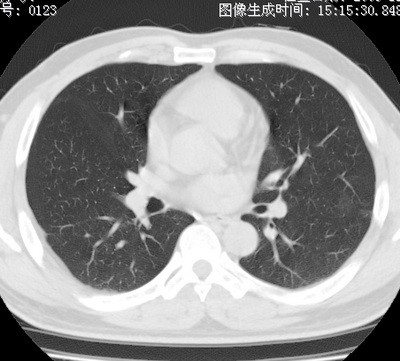

以下是引用zhao_bin2008在2010-1-4 20:15:00的发言:[br]先天性肺囊肿或小的肺隔离症?

以下是引用卜一在2010-1-4 22:09:00的发言:[br]先天性肺囊肿或小的肺隔离症?支持!

以下是引用zsl6918在2010-1-5 5:23:00的发言:[br]良性改变!肺囊肿,先天性支气管闭锁,血管畸形等均有可能。

以下是引用影像之路在2010-1-6 11:10:00的发言:[br]腺癌,最终的病检有些出乎意料之外,术前同志们大多考虑为肺囊肿或小的肺隔离征 [br]回过头来看 小结节呈分叶状,其内侧有一条较粗的静脉供血或许能成为支持诊断腺癌的理由